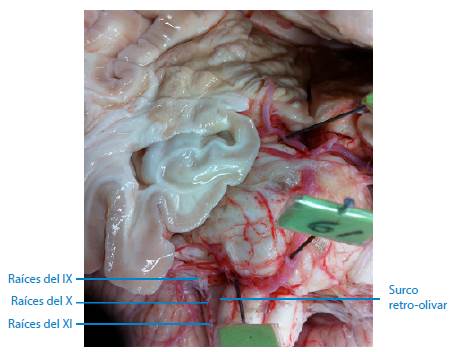

De los 67 troncos encefálicos estudiados, se encontró que en ninguno de ellos las raíces nerviosas de los nervios glosofaríngeo, vago y accesorio hacían su aparición como origen aparente en el surco retro-olivar, tal como se describe en la literatura consultada. Se observó que, en el 100% de las piezas neuroanatómicas estudiadas, el origen aparente de estos tres nervios craneales forma una línea continua de raicillas que se localiza entre 2mm a 3mm por detrás del surco retro-olivar, en sus lados derecho e izquierdo, concretamente en las áreas retro-olivares, tal como se puede apreciar en las Figuras 1, 2, 3 y 4. Además, no se evidencia ningún surco en aquel sitio por donde emergen las raicillas de estos nervios craneales.

Múltiples autores indican que el origen aparente de los nervios glosofaríngeo, vago y accesorio se encuentra en el surco retro-olivar 5,6,18,19 o surco post-olivar 7,9,20. Sin embargo, una inspección más detallada en las muestras estudiadas sobre dicho sitio de origen revela que tal descripción no es cierta y carece de precisión, por lo que se sugiere hacer más estudios en otros lugares geográficos y con una muestra mayor, esto con el fin de precisar dicho sitio de emergencia o revaluar este concepto. En los 67 troncos encefálicos utilizados para este trabajo, se encontró que en ninguno de ellos las raicillas nerviosas de estos nervios craneales emergen por los surcos retro-olivares. En el 100% de las piezas neuroanatómicas analizadas, se evidenció y registró fotográficamente que las raicillas nerviosas hacen su aparición entre 2mm a 3mm por detrás del surco retro-olivar en sus lados derecho e izquierdo, concretamente en las áreas retro-olivares; además, contrario a lo que se registra en la literatura, no se observó la presencia de ningún surco en aquel sitio por donde emergen las raicillas nerviosas.

Los nervios craneales glosofaríngeo, vago y accesorio no tienen su origen aparente en el surco retro-olivar, como tradicionalmente se describe en los textos y artículos referenciados. El verdadero origen aparente de estos nervios ocurre entre 2mm a 3mm por detrás del surco retro-olivar, lugar donde se aprecia una línea continua de raicillas nerviosas que se hacen visibles en ambos lados de la médula oblongada, en específico en las áreas retro-olivares. Tampoco se encontró evidencia de ningún surco en el sitio donde supuestamente emergen las raicillas de estos nervios craneales, distinto a lo que se describe en la literatura.